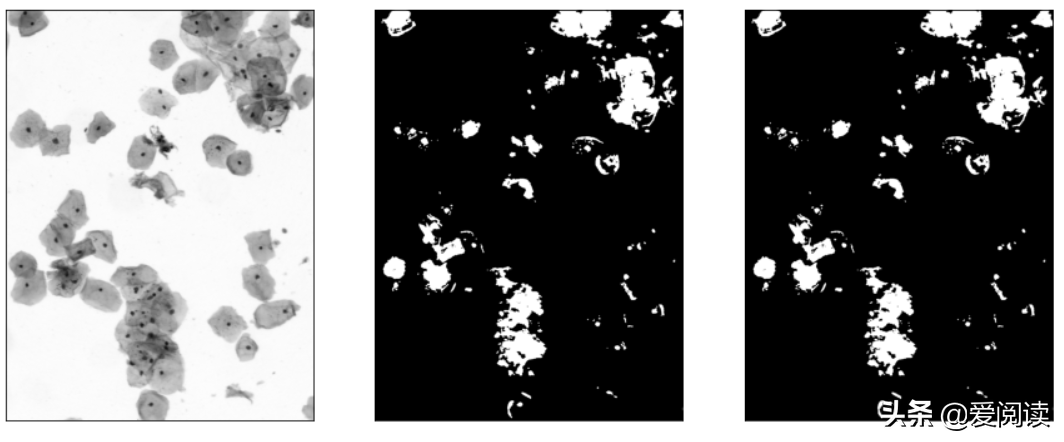

plt.subplot(131), plt.imshow(img_gray, 'gray'), plt.xticks([]), plt.yticks([])

plt.subplot(132), plt.imshow(img_hsv, 'gray'), plt.xticks([]), plt.yticks([])

plt.subplot(133), plt.imshow(bw_cell, 'gray'), plt.xticks([]), plt.yticks([])

plt.show()

你试过吗?图像(细胞)分割